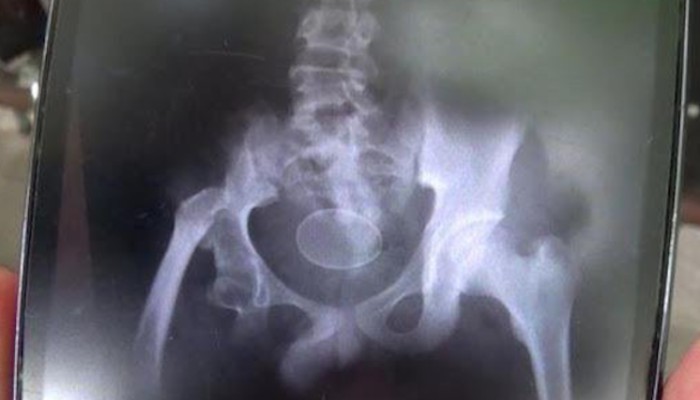

Ο 29χρονος φόργουορντ αγωνίζεται εδώ και αρκετό καιρό με πρόβλημα στο δάχτυλο και ενοχλήσεις στη μέση. «Σφίγγει», όμως, τα δόντια και παλεύει. Κόντρα στους «κιτρινόμαυρους» έκανε μια πολύ καλή εμφάνιση (18π., 6ρ., 2ασ., 1κλ.), η οποία, όμως δεν έφτανε, για να του απαλύνει για λίγο τον... πόνο. «Δεν μου δίνει αισιοδοξία να σου πω την αλήθεια. Είναι πολύ δύσκολη η συνέχεια για εμάς. Είμαστε στις τελευταίες θέσεις του πρωταθλήματος... Έχουμε πολύ δύσκολο έργο ακόμα», λέει και προσθέτει για τον στόχο της παραμονής στην Α1: «Έχουμε ξεκινήσει να το σκεφτόμαστε εδώ και πολύ καιρό, όχι τώρα. Αλλά τι να κάνουμε; Πρέπει να προσαρμοστούμε στις δύσκολες συνθήκες. Να δούμε τι μπορούμε να σώσουμε».